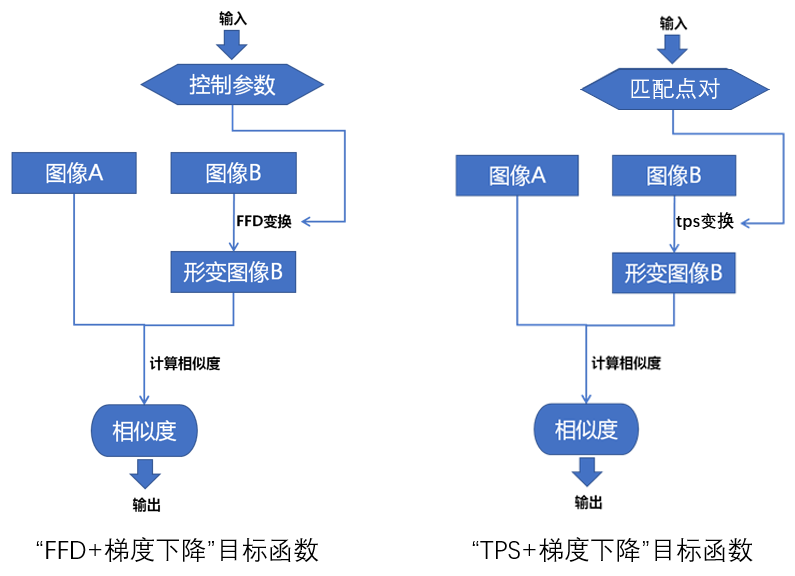

同时我们前面也讲过梯度下降法优化算法的原理,以及基于FFD变换与梯度下降法的图像配准方法:

前文我们讲基于FFD变换的配准方法时,有说过目标函数为:计算参考图像与经过FFD变换之后的浮动图像的互相关系数。基于tps变换与梯度下降法的配准方法也类似,也即计算参考图像与经过tps变换之后的浮动图像的互相关系数,如下图所示:

由上图可知,此时目标函数的输入参数由FFD控制参数变成了参考图像与浮动图像的匹配点对,变换模型由FFD变成了tps。